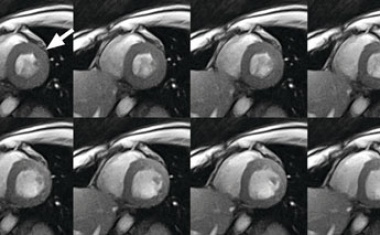

Neue Therapieoption für Patienten mit Herzschwäche und verminderter Pumpfunktion

Bisher mussten sich Patienten mit einer Herzmuskelschwäche mit eingeschränkter Pumpfunktion nach drei Monaten einen Defibrillator implantieren lassen, um ihr Überleben zu sichern.